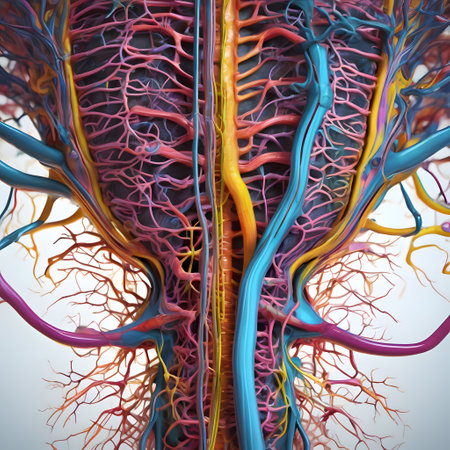

A high-quality close-up of the human nervous system, including spinal cord and nerve connections, displayed with clear and intricate details

Nerve network: nervous system - unraveling the intricate web of neurons and synapses, vital role of this complex system in regulating bodily functions and responses

Detailed anatomical illustration showing the human brain, spine, and nervous system with a focus on the intricate connections between them

Generative AI High-resolution visual representation of the peripheral nervous system (PNS), highlighting nerve bundles and ganglia connecting the CNS to various body parts. photorealistic epic lighting